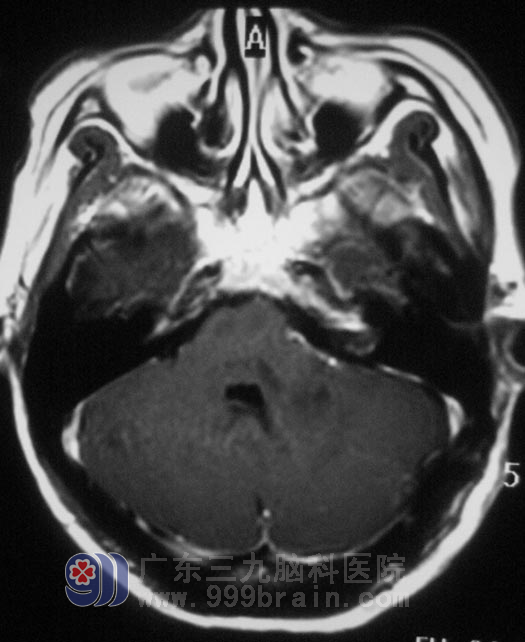

李女士是公司的财务人员,一个月前出现头痛,以左枕部明显,呈阵发性钝痛,以为是年底工作忙,劳累过度所致,休息一周后,头痛也不见好转。当地医院行头颅CT检查,结果示:“左侧小脑、枕叶交界处低密度影,约2.9cm×2.3cm;梗阻性脑积水”。

12月16日,由广东三九脑科医院综合神经外科 鲁明主任主刀,在全麻下行“左侧桥小脑角区肿瘤切除术”。显微镜下见黄白色肿瘤组织,质软,血供丰富,面神经位于肿瘤前下方,副神经、迷住神经、舌咽神经位于肿瘤后下方,神经组织形态菲薄。在显微镜下利用超声刀分块切除,见肿瘤深入内听道,磨钻磨除部分内听道,切除内听道内肿瘤组织,对中后组颅神经保留完整,手术顺利结束。术后李女士经过一段时间的恢复后,梗阻性脑积水情况得到了缓解,听力保存完好,副神经均没有受到影响。术后病理结果为:(左侧桥小脑角)符合听神经瘤。http://www.999brain.com/